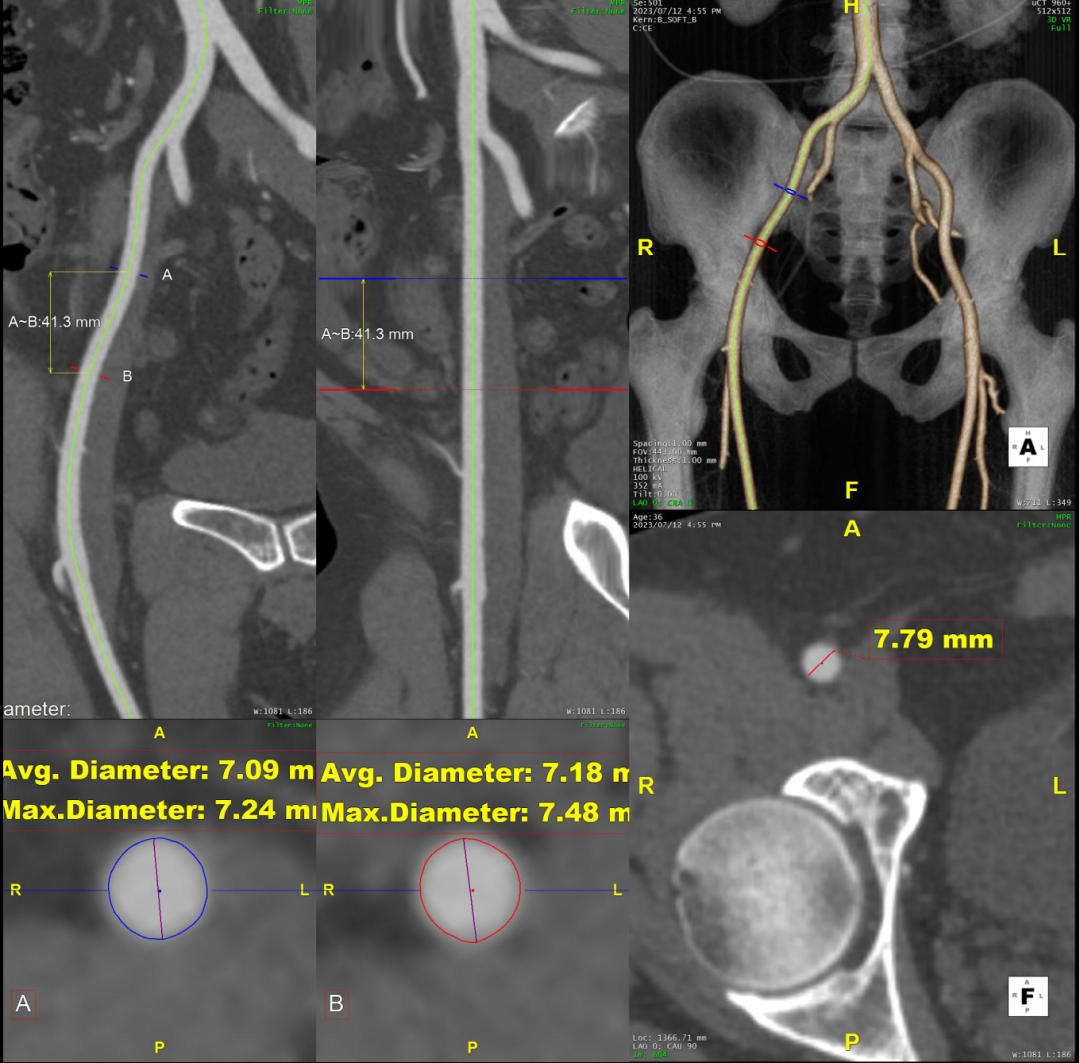

术前CTA评估与测量

术前CTA提示主动脉夹层(Stanford B型,Debake llI型),主动脉弓及降主动脉瘤样扩张,累及左锁骨下动脉起始段,管径最粗约7.4cm,夹层初破口位于降主动脉起始段,向下累及至腹主动脉(约平胸12椎体水平),真腔小,假腔大,腹腔干发自混合腔,肠系膜上动脉、下动脉,双肾动脉均起自真腔,双肾灌注未见差异。

术前三维重建

术前CTA详解: